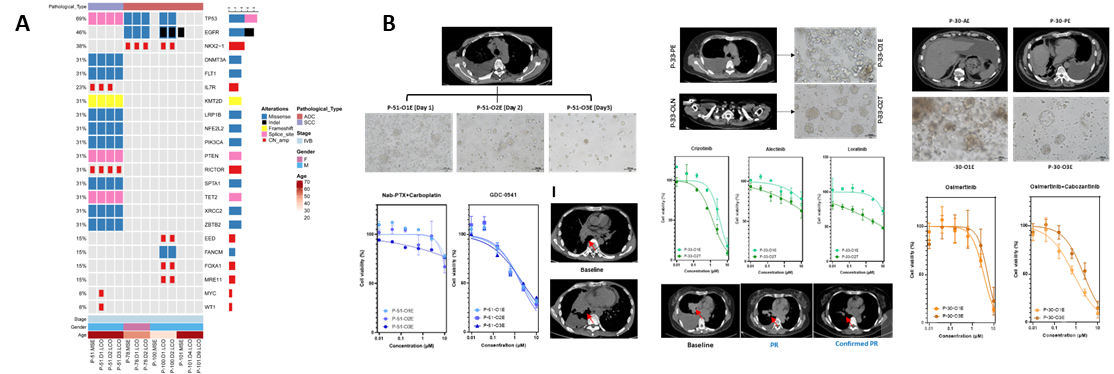

本研究中两例晚期肺腺癌的典型案例:一例EGFR基因突变合并原发MET基因扩增,另外一例EGFR基因突变合并获得性RET基因融合。 相比于单一靶向药物,两例患者的药敏结果均显示联合靶向治疗(奥希替尼+赛沃替尼/卡博替尼)的肿瘤控制率更高,并且在临床治疗中得到证实,双靶联合治疗均达到了部分缓解(PR)的疗效,表明双靶治疗可能是此类双基因变异人群的更优选择(Figure 5)。

Figure 5. LCO预测双靶向治疗的疗效。